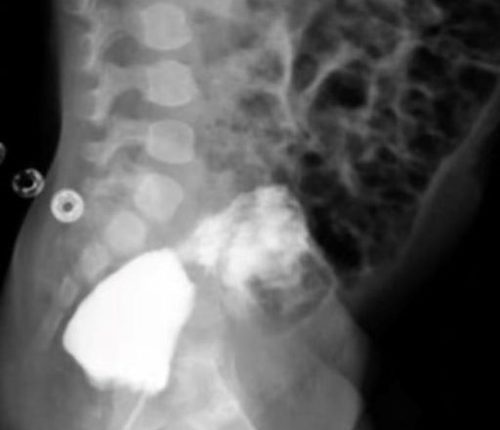

Jelas doktor, pihaknya menjalankan beberapa ujian saringan khas beberapa bulan selepas kanak-kanak itu dilahirkan bagi mengetahui bagaimana sistem urinarinya berfungsi.

Hasil laporan mendedahkan terdapat sambungan fistula yang tidak normal antara pundi kencing dan rektrum kanak-kanak itu.